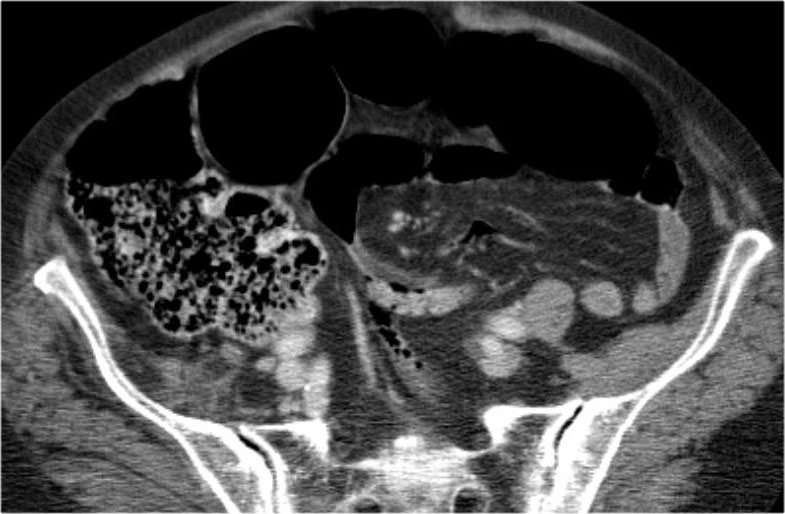

Đây là một trường hợp xoắn đại tràng sigma khác.

Trên X-quang bụng, rất khó nhận biết tình trạng bệnh lý vì có quá nhiều quai ruột giãn.

Tiếp tục với các hình ảnh CT.

Lưu ý điểm chuyển tiếp (mũi tên đỏ).